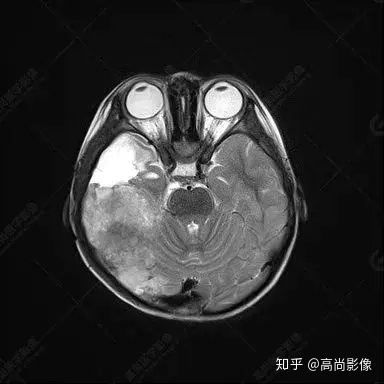

右側(cè)顳葉腫瘤切除術(shù)后(具體不詳):右側(cè)顳部骨質(zhì)不連續(xù)呈術(shù)后改變,右側(cè)顳葉術(shù)區(qū)見片狀長(zhǎng)T1長(zhǎng)T2信號(hào)影,F(xiàn)LAIR呈低信號(hào);術(shù)區(qū)后方右側(cè)顳枕葉見一巨大占位性病變影,邊界欠清,大小約6.2×5.8×4.3cm(前后×左右×上下),信號(hào)不均勻,T1WI呈等稍低信號(hào)間雜少許高信號(hào),T2WI呈高稍低混雜信號(hào),DWI示部分病灶彌散受限,相應(yīng)ADC圖減低,磁敏感序列見部分呈極低信號(hào),增強(qiáng)掃描可見明顯不均勻強(qiáng)化,鄰近硬腦膜及小腦幕增厚并明顯強(qiáng)化;另延髓右前方及右側(cè)橋小腦角區(qū)見一不規(guī)則形異常信號(hào)影,大小約3.2×1.3×3.7cm(左右×前后×上下),呈長(zhǎng)T1稍長(zhǎng)T2信號(hào),F(xiàn)LAIR呈等信號(hào),DWI未見受限,增強(qiáng)后明顯均勻強(qiáng)化,鄰近腦膜明顯強(qiáng)化。鄰近腦實(shí)質(zhì)及右側(cè)顳角明顯受壓;左側(cè)大腦半球未見局灶性信號(hào)異常,中線結(jié)構(gòu)稍左移。

右側(cè)顳葉腫瘤切除術(shù)后:現(xiàn)術(shù)區(qū)后方右側(cè)顳枕葉及延髓右前方占位,右側(cè)顳枕部硬腦膜及小腦幕明顯強(qiáng)化,結(jié)合既往影像資料,考慮為胚胎源性惡性腫瘤,如非典型畸胎樣/橫紋肌樣瘤(AT/RT)或原始神經(jīng)外胚層腫瘤(PNET)。

非典型畸胎樣/橫紋肌樣瘤(AT/RT) 是一種高度惡性中樞神經(jīng)系統(tǒng)腫瘤,臨床罕見,臨床表現(xiàn)無(wú)特異性,好發(fā)于 5 歲以下兒童,尤以 3 歲以下多見,在兒童原發(fā)性中樞神經(jīng)系統(tǒng)(CNS)腫瘤中占 1%~3%。該腫瘤體積一般較大,幕上大于幕下,有明顯的占位效應(yīng)。該腫瘤成分復(fù)雜,囊變、出血、壞死常見。因此 AT/RT信號(hào)混雜,囊性部分呈 T1WI低、T2WI高信號(hào),增強(qiáng)后不強(qiáng)化;若瘤體出血,囊內(nèi)可見T1WI稍高信號(hào)、T2WI低信號(hào),實(shí)性部分在 T1WI上呈混雜等、低信號(hào),在T2WI 及 T2-FLAIR上呈混雜等高信號(hào),增強(qiáng)掃描后大部分呈環(huán)形條帶樣明顯強(qiáng)化,中心壞死區(qū)不強(qiáng)化。另外,該腫瘤實(shí)性成分在DWI上呈高信號(hào),說(shuō)明腫瘤細(xì)胞核密集,水分子擴(kuò)散明顯受限,提示該腫瘤惡性程度高,容易復(fù)發(fā)及轉(zhuǎn)移。